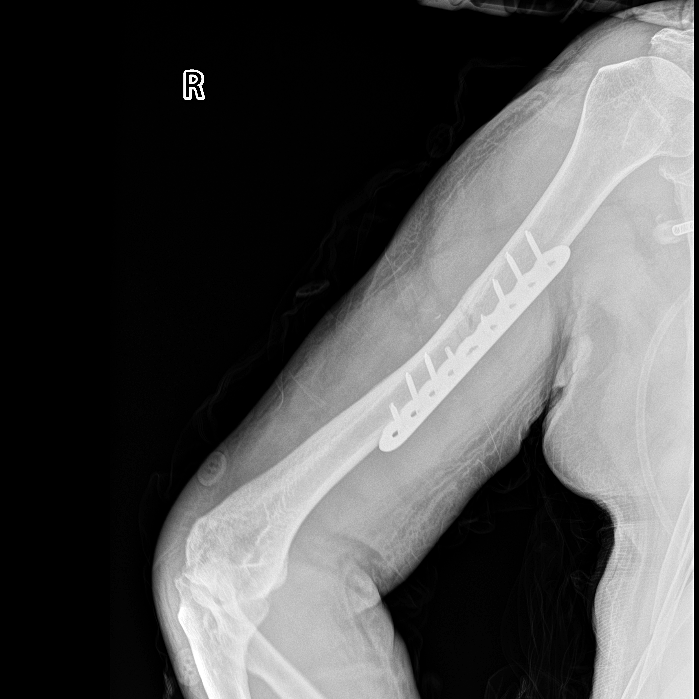

【右肱骨骨折术后】

胸外科医生率先出手,紧急置入胸腔闭式引流管,成功排出压迫肺部的血气胸,为呼吸功能争取喘息空间;神经外科团队紧盯颅内情况,精准用药控制脑挫裂伤引发的脑水肿,严防脑出血恶化;骨科团队则针对右侧肱骨骨折制定手术方案,为后续康复打下基础。